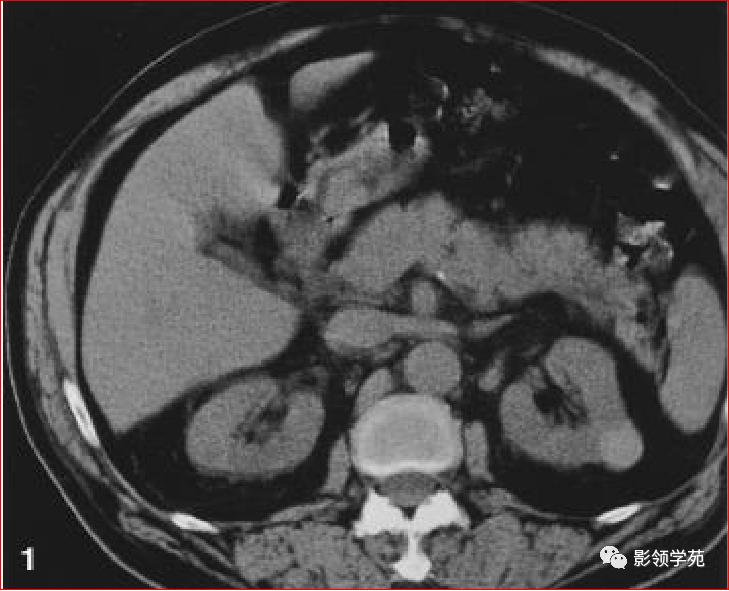

1、单纯性肾囊肿

位于肾皮质内的良性囊性病变。

常多发,大小不一。

呈圆形,壁菲薄光整,内衬扁平上皮,含清亮浆液。

囊肿可位于肾内或突出于肾轮廓外。

增强扫描无强化。